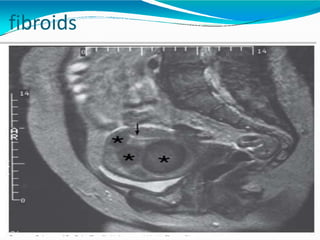

Imaging

⚫Forsymptomaticwomen, consideration of conservative

therapy, non invasive procedureorsurgeryoften depends on an

accurateassessment of the size, numberand position of

fibroids.

⚫TVS Saline infusion USG, Hysteroscopy, MRI can be done. Sub

mucous fibroids were best identified by MRI (100%sensitivity,

91% specificity )

SIS (sensitivity 90%, specificity 89% )

Hysteroscopy (sensitivity 82%, specificity 87%).

⚫MRI allows evaluationof number, size location and proximity

to bladder, rectum, tubal opening in uterine cavity and

endometrium, thus helping in planning surgery.